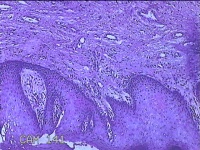

宫颈组织

性别

女

年龄

54岁

临床诊断

宫颈上皮内瘤变Ⅰ级

一般病史

反复阴道脱出肿物3年余。

标本名称

大体所见

灰白暗红色组织4.8x1.5x0.3cm一块,肥大,糜烂,切面灰白粉红色,质软